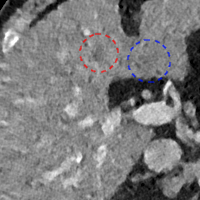

To show the denoising effect of the selected networks, we took two representative slices as shown in Figs. 5 and 7. And Figs. 6 and 8 are the zoomed regions-of-interest (ROIs) marked by the red rectangles in Figs. 5 and 7. All the networks demonstrated certain denoising capabilities. However, CNN-MSE blurred the images and introduced waxy artifacts as expected, which are easily observed in the zoomed ROIs in Figs. 6e and 8e. WGAN-MSE was able to improve the result of CNN-MSE by avoiding over-smooth but minor streak artifacts can still be observed especially compared to CNN-VGG and WGAN-VGG. Meanwhile, using WGAN or GAN alone generated stronger noise (Figs. 6g and 8g) than the other networks enhanced a few white structures in the WGAN/GAN generated images, which are originated from the low dose streak artifact in LDCT images, while on the contrary the CNN-VGG and WGAN-VGG images are visually more similar to the NDCT images. This is because the VGG loss used in CNN-VGG and WGAN-VGG is computed in a feature space that is trained previously on a very large natural image dataset [48]. By using VGG loss, we transferred the knowledge of human perception that is embedded in VGG network to CT image quality evaluation. The performance of using WGAN or GAN alone is not acceptable because it only maps the data distribution from LDCT to NDCT but does not guarantee the image content correspondence. As for the lesion detection in these two slices, all the networks enhance the lesion visibility compared to the original noisy low dose FBP images as noise is reduced by the different approaches.

As for iterative reconstruction technique, the reconstruction results depend greatly on the choices of the regularization parameters. The implemented dictionary learning reconstruction (DictRecon) result gave the most aggressive noise reduction effect compared to the network outputs as a result of strong regularization. However, it over-smoothed some fine structures. For example, in Fig. 8, the vessel pointed by the green arrow was smeared out while it is easily identifiable in NDCT as well as WGAN-VGG images. Yet, as an iterative reconstruction method, DictRecon has its advantage over post-processing method. As pointed by the red arrow in Fig 8, there is a bright spot which can be seen in DictRecon and NDCT images, but is not observable in LDCT and network processed images. Since the WGAN-VGG image is generated from LDCT image, in which this bright spot is not easily observed, it is reasonable that we do not see the bright spot in the images processed by neural networks. In other words, we do not want the network to generate structure that does not exist in the original images. In short, the proposed WGAN-VGG network is a post-processing method and information that is lost during the FBP reconstruction cannot easily be recovered, which is one limitation for all the post-processing methods. On the other hand, as an iterative reconstruction method, DictRecon algorithm generates images from raw data, which has more information than the post-processing methods.